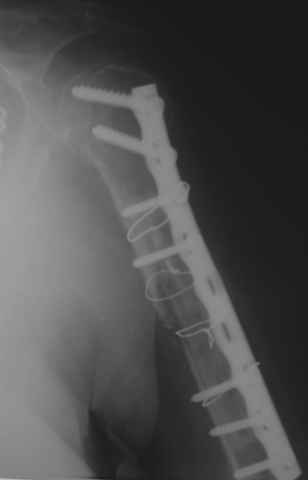

Уважаемые коллеги! На консультации больная 65 лет. С одной рентгенограммой - рис.1.

Анамнез: 30 августа перелом левой плечевой кости, невропатия лучевого нерва - кисть повисла сразу. Лечение по месту жительства - иммобилизация косынкой. 2 октября в одной из больниц города металлоостеосинтез. Все развалилось. 16 октября - повторная операция, через десять дней - картина на рис.1. Далее металлоостеосинтез с костной аутопластикой малоберцовой костью 9 февраля 2009г. Снимки 2-4 выполнены сегодня.

Считаем, что шансов на приживление и перестройку такого трансплантата в данной ситуации нет. Нестабильность запрограммирована и вываливание этого всего дело ближайшего будущего. Вопросы для обсуждения: